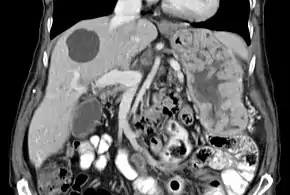

| Biopsy of the stomach in Ménétrier disease showing the substantial pit hyperplasia makes the large rugal folds appear to be covered by myriad polyps resembling hyperplastic polyps. The muscularis propria is the folded structure at the bottom center. | |

With Ménétrier disease, the stomach is characterized by large, tortuous gastric folds in the fundus and body, with the antrum generally spared, giving the mucosa a cobblestone or cerebriform (brain-like) appearance.[5] Histologically, the most characteristic feature is massive foveolar hyperplasia (hyperplasia of surface and glandular mucous cells).[3] The glands are elongated with a corkscrew-like appearance and cystic dilation is common. Inflammation is usually only modest, although some cases show marked intraepithelial lymphocytosis. Diffuse or patchy glandular atrophy, evident as hypoplasia of parietal and chief cells, is typical.[4]